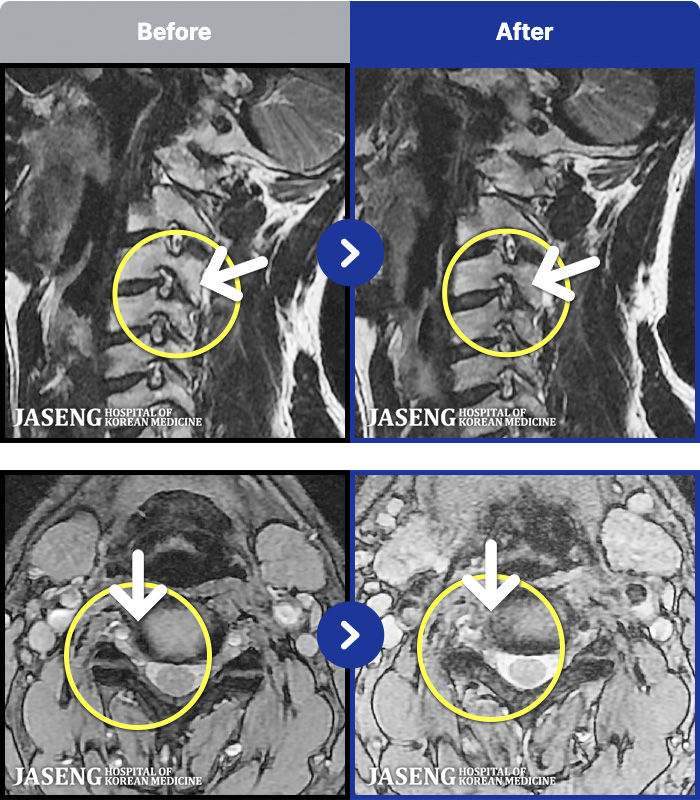

54 MRI ũ ʸ Ȯϼ.